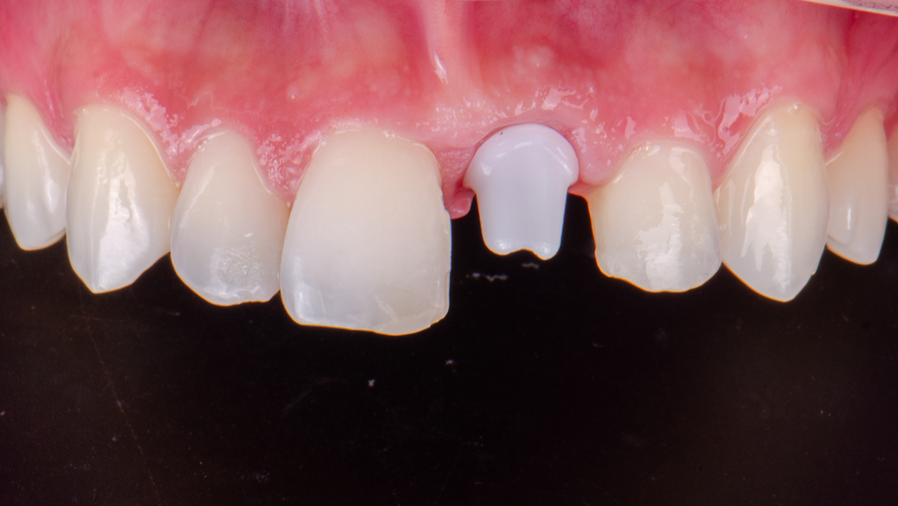

Paciente jovem, do sexo masculino, sistemicamente saudável, apresentou-se para reabilitação da região do dente 21, perdido devido a uma lesão cariosa extensa e irreversível.

A intervenção cirúrgica teve início com a exodontia atraumática do dente 21. Inicialmente foi realizada uma coronectomia, seguida da remoção cuidadosa do fragmento radicular, com a preservação integral das tábuas ósseas.

A perfuração inicial para instalação do implante foi realizada com uma broca lança helicoidal, acoplada a prolongador, seguida da verificação do paralelismo com o Túnel Check (Implacil Osstem). Após confirmação do eixo adequado, procedeu-se com a fresagem sequencial com a fresa de 3,0 mm, e nova conferência da angulação foi realizada.

Foi então instalado um implante Due Cone Maestro CM 3,5 x 11 mm (Implacil Osstem), respeitando o posicionamento previamente planejado. A estabilidade primária foi medida com o Osstell, equipamento que utiliza a tecnologia de ressonância magnética para aferir a estabilidade do implante por meio do Implant Stability Quotient (ISQ). Essa métrica fornece uma estimativa objetiva do grau de ancoragem inicial entre o implante e o osso adjacente, sendo um importante parâmetro para indicar ou contraindicar a carga imediata. No presente caso, o valor obtido foi considerado insuficiente, levando à decisão de instalar o tapa-implante e permitir a cicatrização submersa durante o período de osseointegração.

Com o objetivo de preservar o volume ósseo e a morfologia gengival, foi realizada uma regeneração óssea guiada (ROG) com o Extra Graft XG-13 aplicado na região vestibular para preenchimento do GAP entre o implante e a parede óssea. Na sequência, foi colocada uma membrana Cytoplast, em PTFE de alta densidade, adaptada sob o tecido gengival e estabilizada por sutura com nylon azul, promovendo selamento do sítio cirúrgico.

Para preservar a estética durante a fase de osseointegração, foi confeccionado um provisório impresso em 3D, previamente planejado no Exocad. Esse provisório, cimentado com auxílio de aletas adesivas nos dentes 11 e 22, apresentava adaptação passiva e promovia pressão controlada sobre os tecidos moles, favorecendo a manutenção da margem gengival e do perfil de emergência. Além disso, por não exercer carga funcional direta sobre o implante, permitiu uma osseointegração segura, sem interferência de forças mastigatórias durante o período crítico de cicatrização.